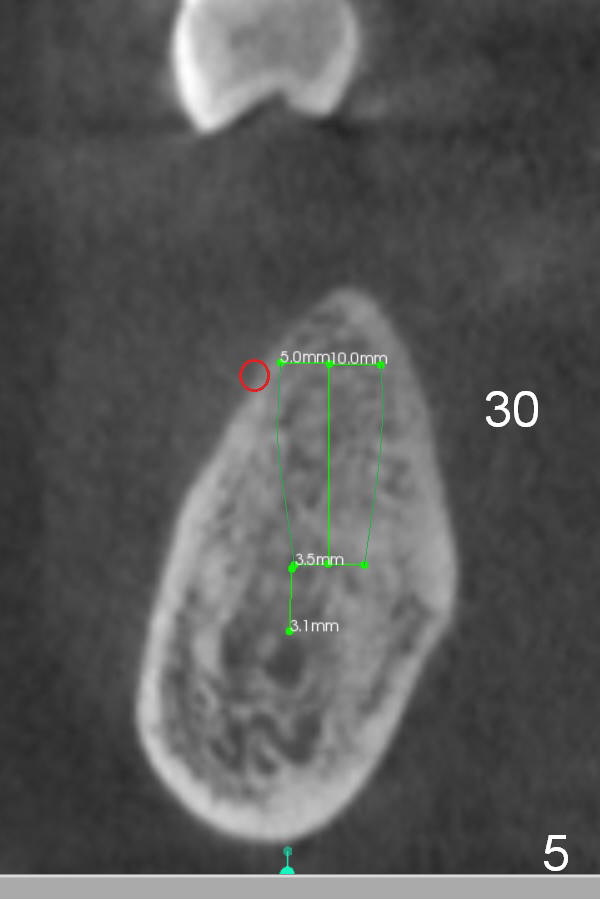

Chief complaint of a 69-year-old lady is "I cannot eat after bottom right bridge removal" (Fig.1). Exam reveals that the tooth #15 is also missing (Fig.2). Four implants are planned. CBCT shows low density of #31 socket (Fig.3,4, bone expanders) and the buccal coronal portion of the #29 socket (Fig.3,6,7, place implant as lingual as possible). The alveolus at the site of #30 is atrophic coronally (Fig.5). If insertion torque of individual implants is reasonably high, an immediate provisional bridge will be fabricated.